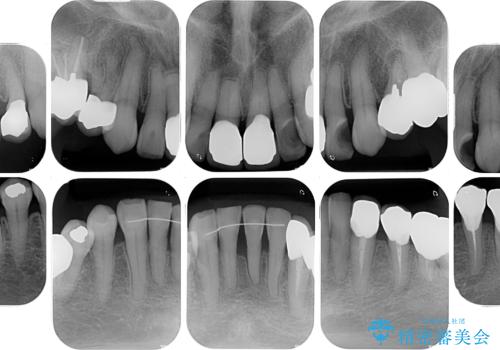

- 長年気にしていた捻れた前歯が欠けたとのことで来院された患者様です。

矯正治療に抵抗があったそうですが、前歯が欠けたことをきっかけに、矯正治療で歯列を整えた上で、セラミッククラウン治療を行う決心が付いたとのことでした。

デコボコが強いため、ブリッジや残根となっている部分のスペースを利用して歯列を整え、変色や欠けている歯をオールセラミッククラウンによる補綴治療を行うこととしました。